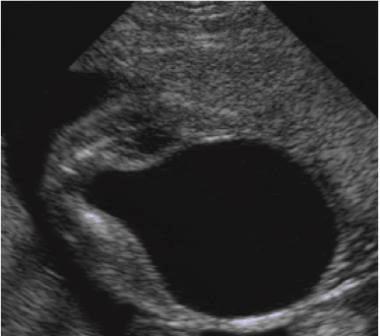

hydronephrosis

What is hydronephrosis usually caused by?

UPJ or UVJ obstruction

What is hydronephrosis?

Dilation of the renal pelvis due to blockage

Pyelectasis

What is pyelectasis?

abnormal collection of urine within the renal pelvis 5-9 mm

Caliectasis

Caliectasis

What is calyectasis?

rounded calyces with renal pelvis dilatation

What is the most common cause of hydronephrosis in neonates?

UPJ obstruction

What is the sonographic appearance of ureteropelvic junction obstruction?

will often show a dilated renal pelvis